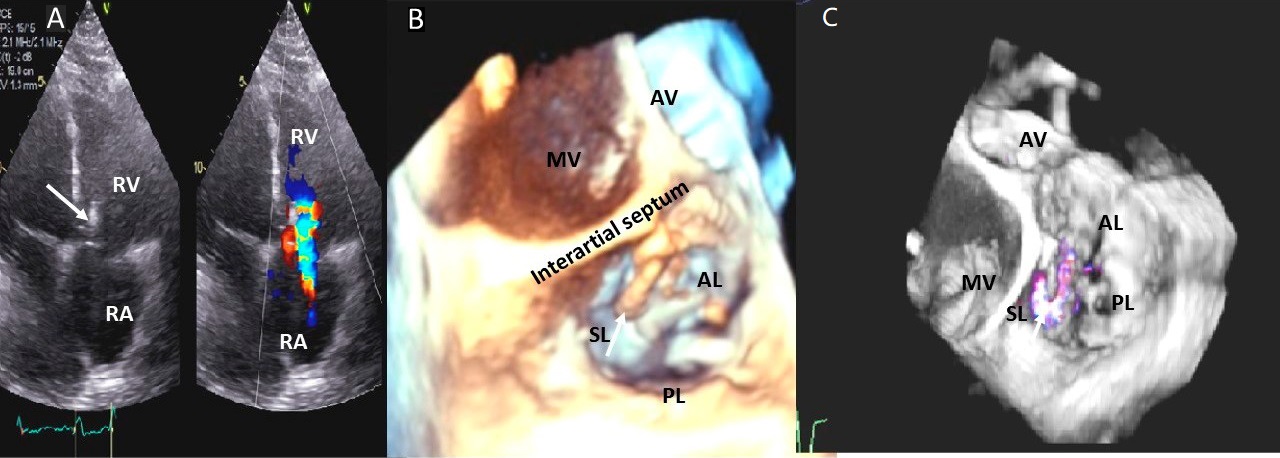

Examples of valvular injury directly from implantable cardioverter-defibrillator lead placement (Fig. 5A–C) or a permanent pacemaker (Fig. 6A–C) or endomyocardial biopsy in cardiac transplant recipients (Fig. 7A,B) are shown.

Fig. 6.Tricuspid regurgitation induced by pacemaker lead valve perforation. (A) Transthoracic 2D 4 chamber view showing pacemaker lead going through the TV leaflet (white arrow) and causing TR. (B) 3D enface view of the TV from the right atrial perspective showing the pacemaker lead going through the margin of the septal leaflet (SL) of the TV (white arrow). (C) 3D color Doppler view of the TV from the atrial perspective showing origin of TR at the site of leaflet perforation. MV, mitral valve; AV, aortic valve; PL, posterior leaflet; AL, anterior leaflet